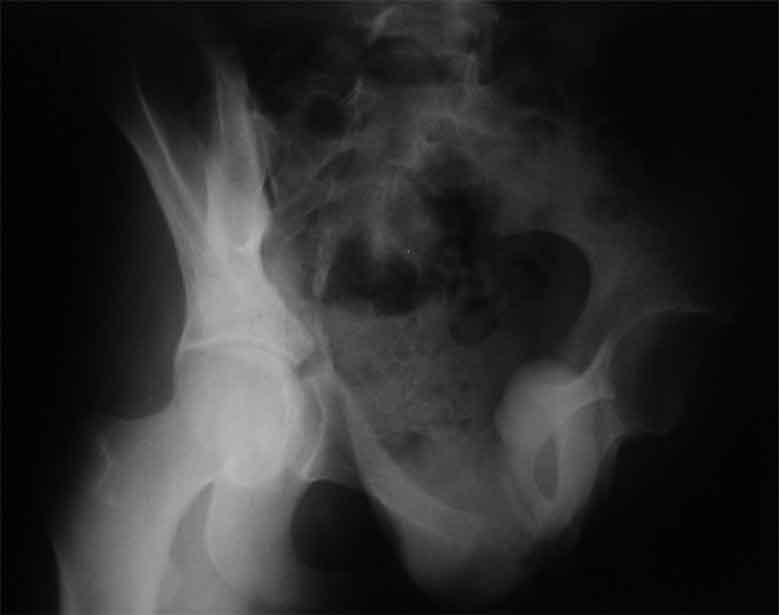

продолжение темы. не увидел энтузиазма в обсуждении. Вопросы прежние, первым этапом закрыто устранили вертикальное и передне-заднее смещение. Каким образом восстановить целостность тазового кольца, из каких доступов? Снимки в приложении

передне-неружным внебрюшинным доступом к лонно-седалищномц сочленению - синтез штангами(можно из заднего доступа, но хуже обзор и труднее репозиция), из этого же доступа к крыше вертлужной впадины - синтез реконструктивными пластинами(мы делали "ChM" тазовыми, хорошо себя зарекомендовали), передним доступом на лонное сочленение - синтез подобной пластиной. к задней колонне вертлужной впадины - задне-наружный доступ, синтез такой же пластиной. КРОВОПОТЕРЯ!!! возможно до 7л. мощная ангтибак. профилактика во время и после операции. до перехода на заднюю колонну оперировать в аппарате. бвл подобный случай, по снятии аппарата через 8 мес. - рецедив смещений сразу.